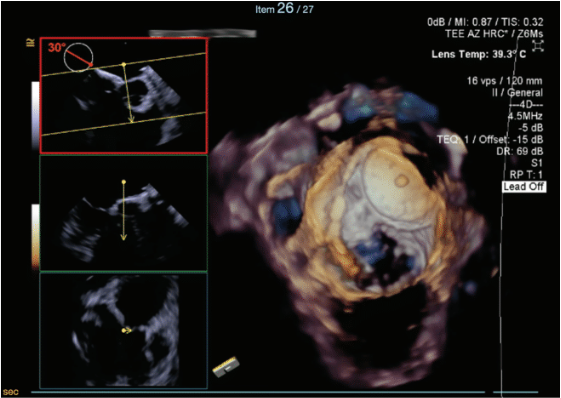

Due to the complexity of the transseptal puncture, the decision was made to have 2 operators perform the case. To ensure the most accurate visualization of the ASD occluder and the target puncture site, 4-dimensional TEE was utilized as a guide.

Two transseptal punctures were attempted, but due to the large, nearly occlusive ASD device, only a single transseptal access was secured. A 98-cm Brokenbrough needle and electrocautery was utilized to localize the posterior superior lip of the available fossa. After transseptal access, the sheath was then advanced over a 0.35” J-wire into the LA. Using the Agilis sheath, a PentaRay diagnostic catheter (Johnson & Johnson MedTech) was advanced into the LA and the entire LA was mapped. The SL-1 sheath was kept in the right atrium (RA) with irrigation.